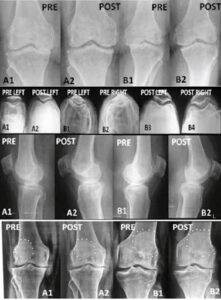

We developed the treatment called pulse radio frequency of the entire nerve supply of the knee, which includes the femoral nerve, (supplies quadriceps) sciatic nerve (supplies hamstrings, popliteus, calf and shin muscles) saphenous nerve (supplies sartorius, a notoriously painful muscle in OA knee) and in patients who have inner thigh pain the obturator nerve. There are three nerve plexuses the Peri Patellar, Sub sartorial and popliteal plexus which are also treated with PRF. Usually, after this PRF, we find that patients report 30 to 50% relief of their pain and stiffness and also the swelling within 2-3 days. We even find that the gap between the two bones’ femur and tibia widens after PRF to relieve the friction between the bones grinding and wearing out the cartilage.

We start the ultrasound guided dry needling a week later. With this treatment patients are able to walk a lot more without pain and also climb stairs without pain. We usually ask the patient to start increasing their walking, standing and climbing steps gradually since these activities may cause some pain occur recurrence but the next session of ultrasound guided dry needing relieves this pain, allowing them to increase their functionality within a month or two. We have reported this as a publication in the international journal called Pain Physician. Hundreds of patients have benefited from this treatment since 2005 and live an active life. This is useful in patients in early and medium stages of osteoarthritis without too much joint damage.

and in patients who are unfit for surgery and also in young patients, who would like to keep their own knees for some more years, and strengthen their knees before eventual knee replacement. We have also treated some patients with severe osteoarthritis who did not want to have surgery. We explained to them that their knee require surgery, but if they want to avoid surgery at any cost then we have helped them. In the past 20 years all such patients had good pain relief, but only 10 could not increase their activity and were advised to have surgery. Because the PRF and USGDN has already relieved the neuromyopathy of OA knee these patients could lead an active life after knee replacement.

This PRF followed by ultrasound guided dry needing is extremely useful, even in patients who suffer from persistent pains even after surgery of knee replacement. Nearly 21% patients continue to have pain in the first 6 months after surgery and about a7% have pain restricting their activity even later. We have published another article on the use of PRF and USGDN for relieving pain after knee replacement surgery In fact, this treatment was developed for many such patients who had failed to get pain relief after knee replacement and we later started using the technique to patients, with pain and distress from OA knee .